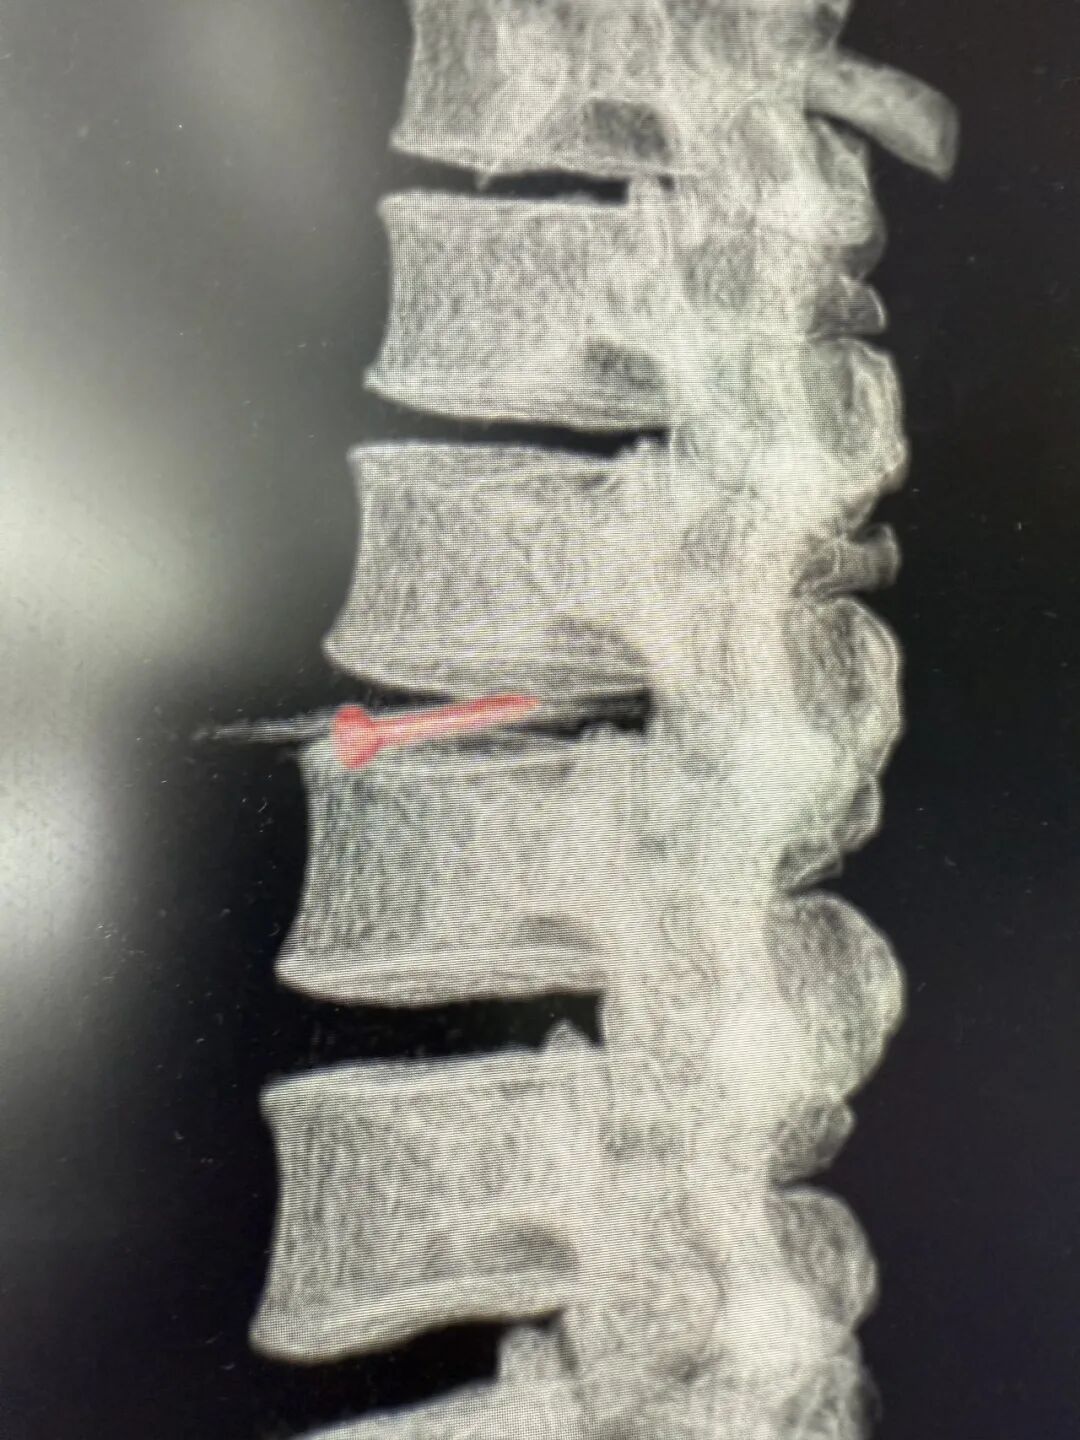

CT影像检查显示

其腰椎间盘里卡竟着一枚

长约3cm的金属钉!

据医生介绍,钉子从腹壁到椎间盘,“走”了约40cm,疑似穿了多个腹腔脏器!

医生称,此枚金属钉依次刺穿腹壁、肝脏左叶、胃壁、结肠系膜、十二指肠、后腹膜,最终嵌插于腰椎间盘内,若处理不好很可能术后出现胆瘘、肠瘘等问题。经过3小时的手术,张师傅体内的钉子终于被取出,且取出后确认是一枚尾部有火药的工程钉。

医生表示,虽然刺穿多个脏器,imtoken钱包官方app下载不过幸运的是,钉子穿过腹部时,并未伤及各大血管,并且正好钉在椎间盘之间,未伤及脊髓。